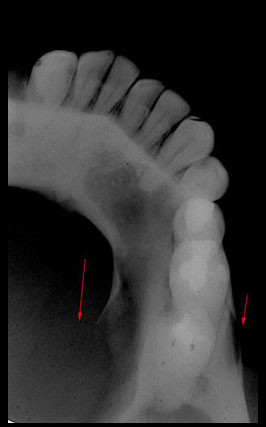

Caso N° 207: AMELOGÉNESIS IMPERFECTA

Paciente de sexo masculino de 40 años de edad acude a la consulta radiológica previo tratamiento protésico. Al examen intraoral se observó una alteración en el color de los dientes notándose amarillento parduzcos así como de la morfología coronal de las piezas dentarias de forma generalizada, además, de presentar superficies de forma irregular. En la radiografía panorámica digital observamos (Fig.1) una disminución generalizada en el espesor del esmalte dentario así como la ausencia de cúspides. En las radiografías periapicales (Fig. 2) confirmamos las características antes descritas.